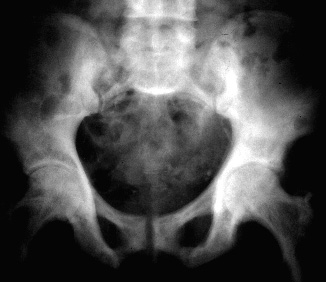

Síndrome de Paget

O Síndrome de Paget é uma doença óssea metabólica, de origem desconhecida embora esteja relacionada com infecções virais e herança genética. Costuma afectar sobretudo a região pélvica, fémur, tíbia, vértebras, clavícula e úmero.

Caracteriza-se pela destruição do tecido ósseo, que volta a formar-se a seguir mas com deformidades.

O novo osso que se forma é estruturalmente maior porém mais fraco, e com muita calcificação.